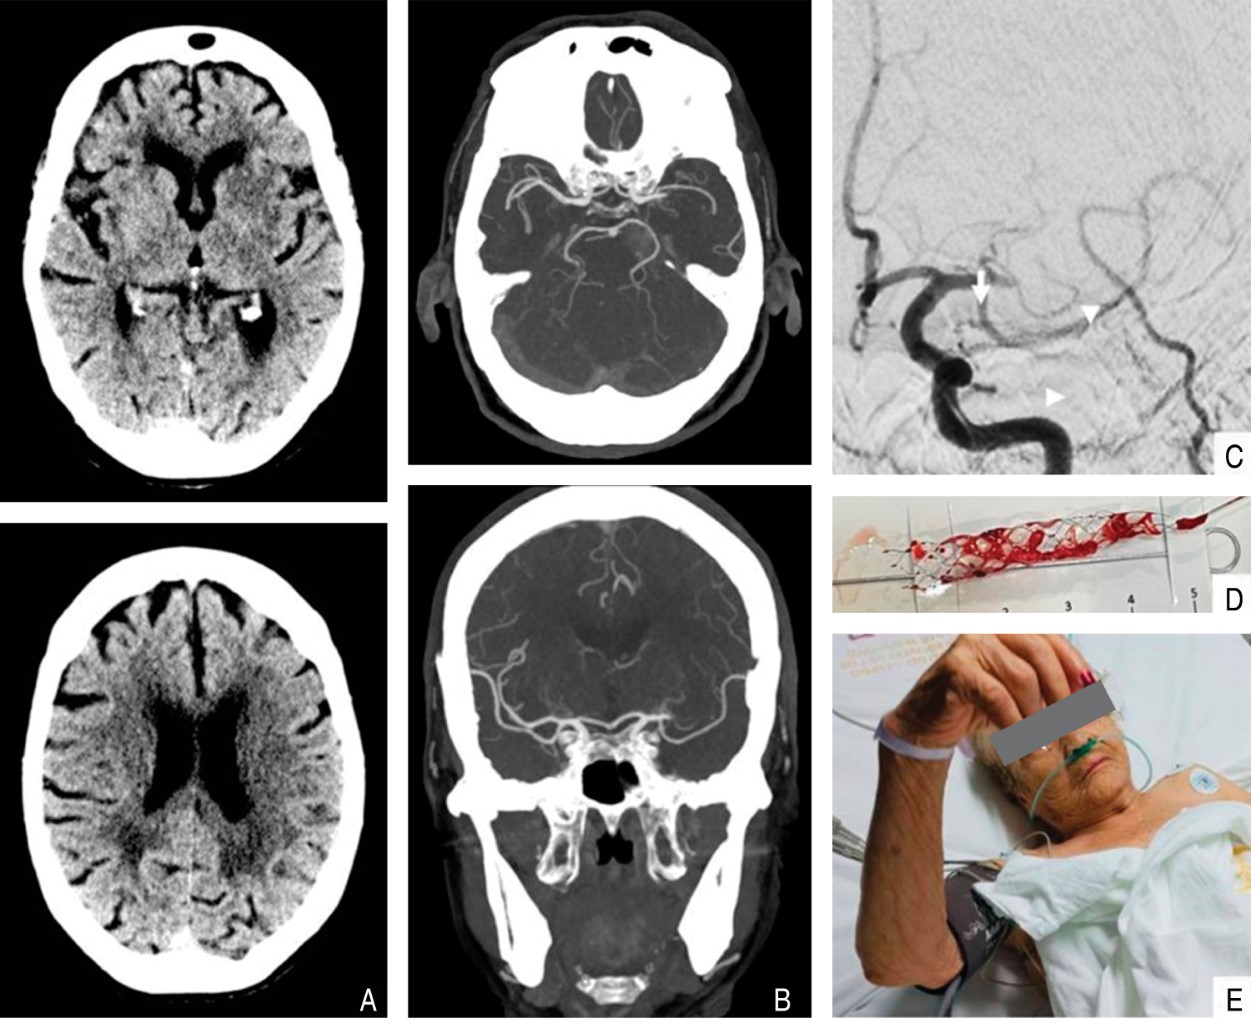

Figura 1